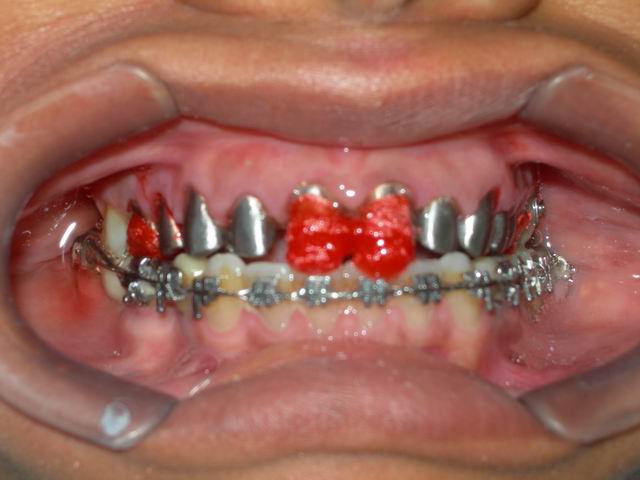

Fase de prova em boca e transferência dos copings metálicos para modelo de trabalho para adição de porcelana dental (vista frontal)

Caso finalizado com cerâmica aplicada em ambas as arcadas (vista frontal)